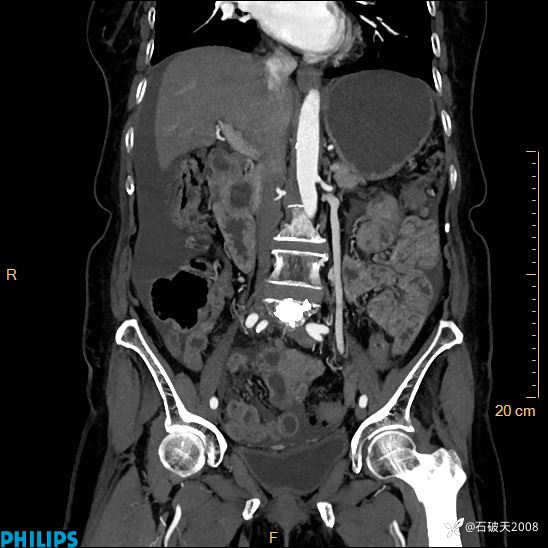

半年前住院没发现问题,近期腹痛来诊

女82岁 主 诉:腹痛半月,加重3天

动脉期